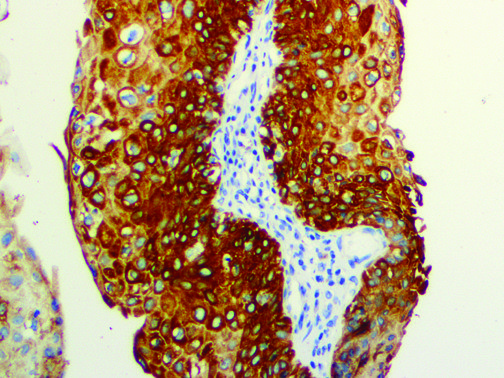

It is the ICU physician who is most likely to witness one of the deadliest manifestations of the abnormal immunological response, the cytokine storm syndrome (CSS). This response is also referred to by some as the cytokine release syndrome (CRS). CSS is characterized by continuous activation and expansion of macrophage and lymphocyte populations, which secrete large amounts of cytokines, causing the cytokine storm. This massive cytokine release is akin to hemophagocytic lymphohistiocytosis (HLH) disease, a syndrome characterized by initial unchecked and persistent activation of cytotoxic T lymphocytes and NK cells.

Clinical and laboratory manifestations of HLH include fever, enlarged liver and/or spleen, neurologic dysfunction, coagulopathy, liver dysfunction, cytopenias (i.e., low levels of erythrocytes, leukocytes, and/or platelets), hypertriglyceridemia, hyperferritinemia, hemophagocytosis, and eventually diminished NK cell activity as the immune system becomes progressively paralyzed. HLH can be familial (primary HLH) or secondary to another disease process (sHLH), such as rheumatic disease, in which it is referred to as macrophage activation syndrome (MAS, characterized by elevated ferritin).